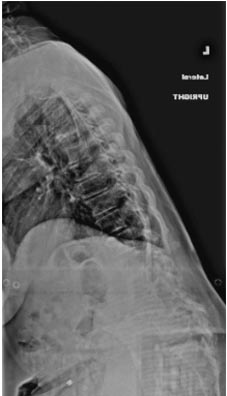

59 year old woman with Scholiosis with severe back pain.

1 year postop from surgery and pain free.